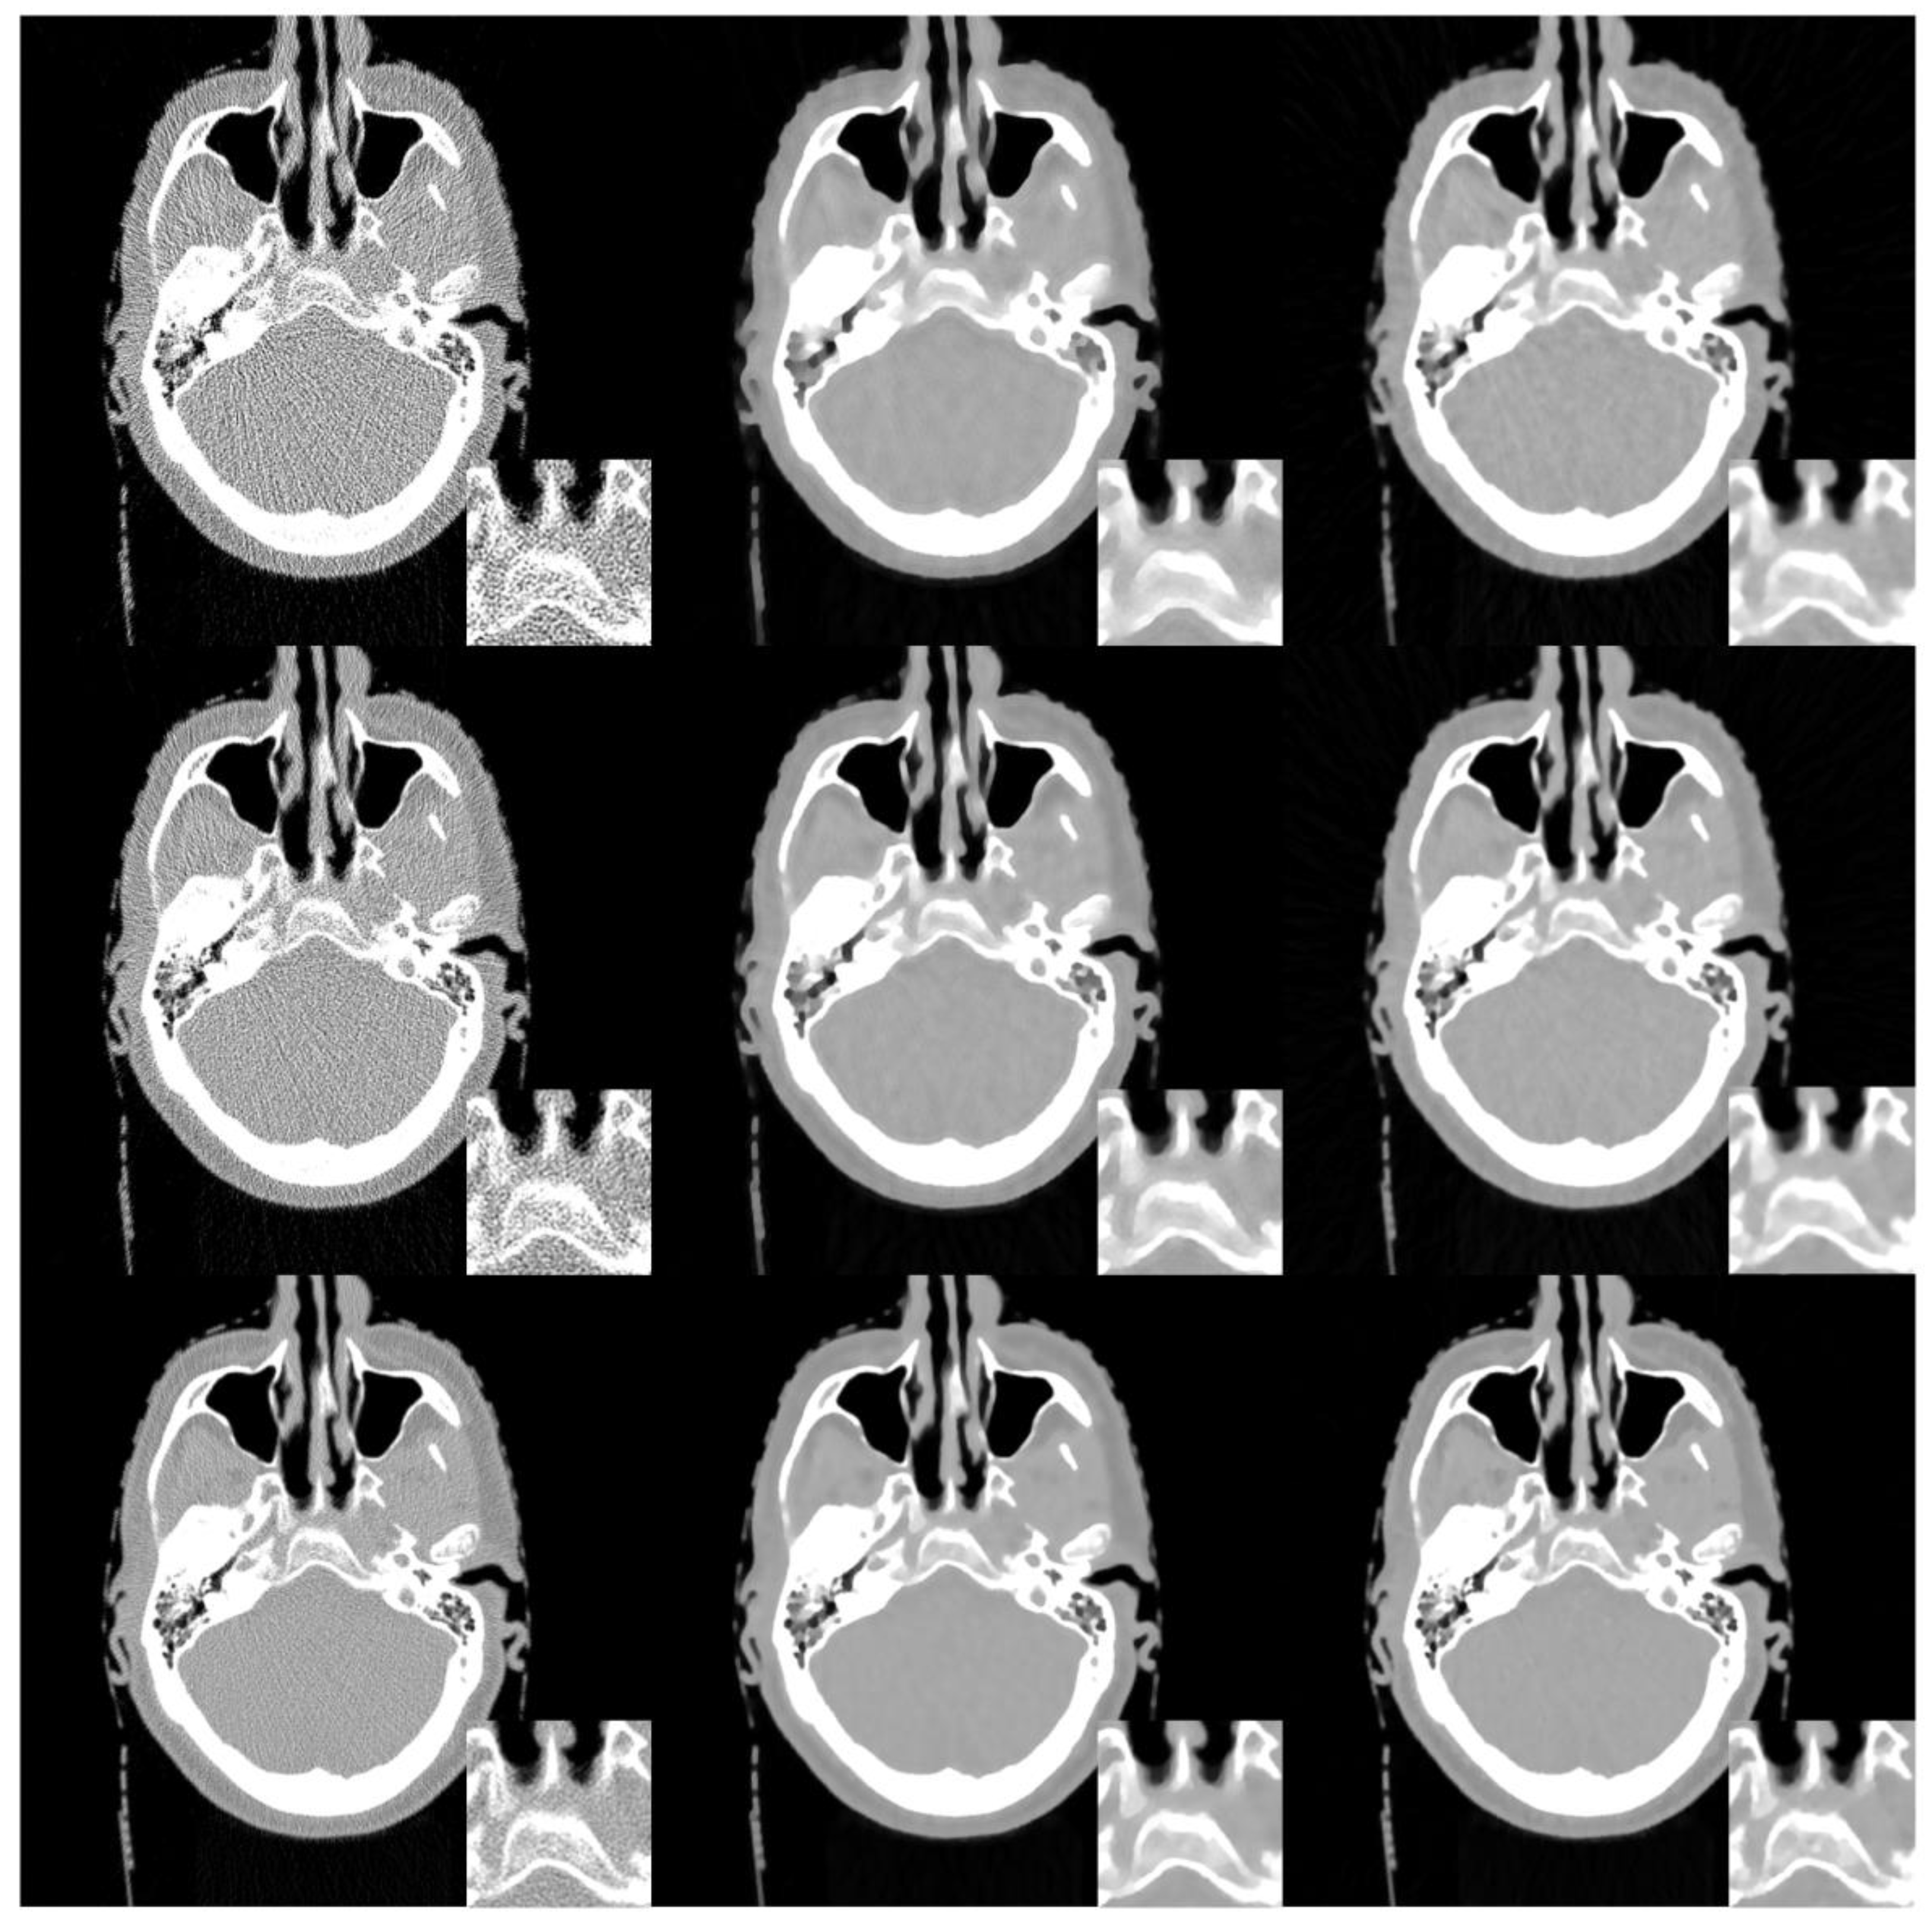

3.3. Realistic Sheep Lung Experiments

To validate the effectiveness of our proposed method for real data, an anesthetized sheep lung was scanned at normal and low dose, respectively on a SIEMENS Somatom Sensation 64-Slice CT Scanner in a circular cone-beam scanning mode. A scan protocol was developed for low dose studies with ECG gating: Time point 1 for a normal X-ray dose scan (100 kV/150 mAs) before a contrast agent injection, and time points 2–21 for low dose scans (80 kV/17 mAs) after the contrast agent injection. All the sinograms of the central slice were extracted, which were in a fan-beam geometry. The radius of the trajectory was 57 cm. A total of 1160 projections were uniformly collected over a 360° range. For each projection, 672 detector elements were equi-angularly distributed to define a FOV of 25.05 cm in radius. In this experiment, the reconstructed images were 768 × 768 pixels with a physical size of 50 × 50 cm. To further demonstrate the performance of our proposed method for a few views of CT reconstruction, 580 and 290 views projection were uniformly exacted form 1160 views projection. In our proposed algorithm, σ = 0.5 , L K = 3. For the reconstruction from noisy projections with 1160, 580, and 290 views, the parameter λ were set as 5 × 10−6, 7 × 10−6, and 2 × 10−5, the number of subset were set to 40, 20, and 10, respectively.

The reconstruction results are presented in Figure 10. It can be seen that the FBP results look very noisy and became worse and worse when the number of projection views decreased from 1160 to 290. Both the SIR-TV and our SIR-STV1 method outperform the FBP algorithm in suppressing image noise. To clearly compare the reconstruction performance of all algorithms, ROIs are extracted from Figure 10 and magnified in Figure 11. From Figure 11, especially denoted by red arrow regions, we can observe that the SIR-TV method produces patchy artifacts obviously, while the SIR-STV1 method could avoid the patchy artifacts effectively.

Figure 10. Images reconstructed by the FBP (left column), SIR-TV (middle column), and SIR-STV1 (right column) methods from low dose projections with 1160 views (the first row), 580 views (the second row, and 290 views (the third row). The display window is [−1000, 800] HU.

Figure 11. Zoom in view ofregion of interest(ROI) in Figure 10.